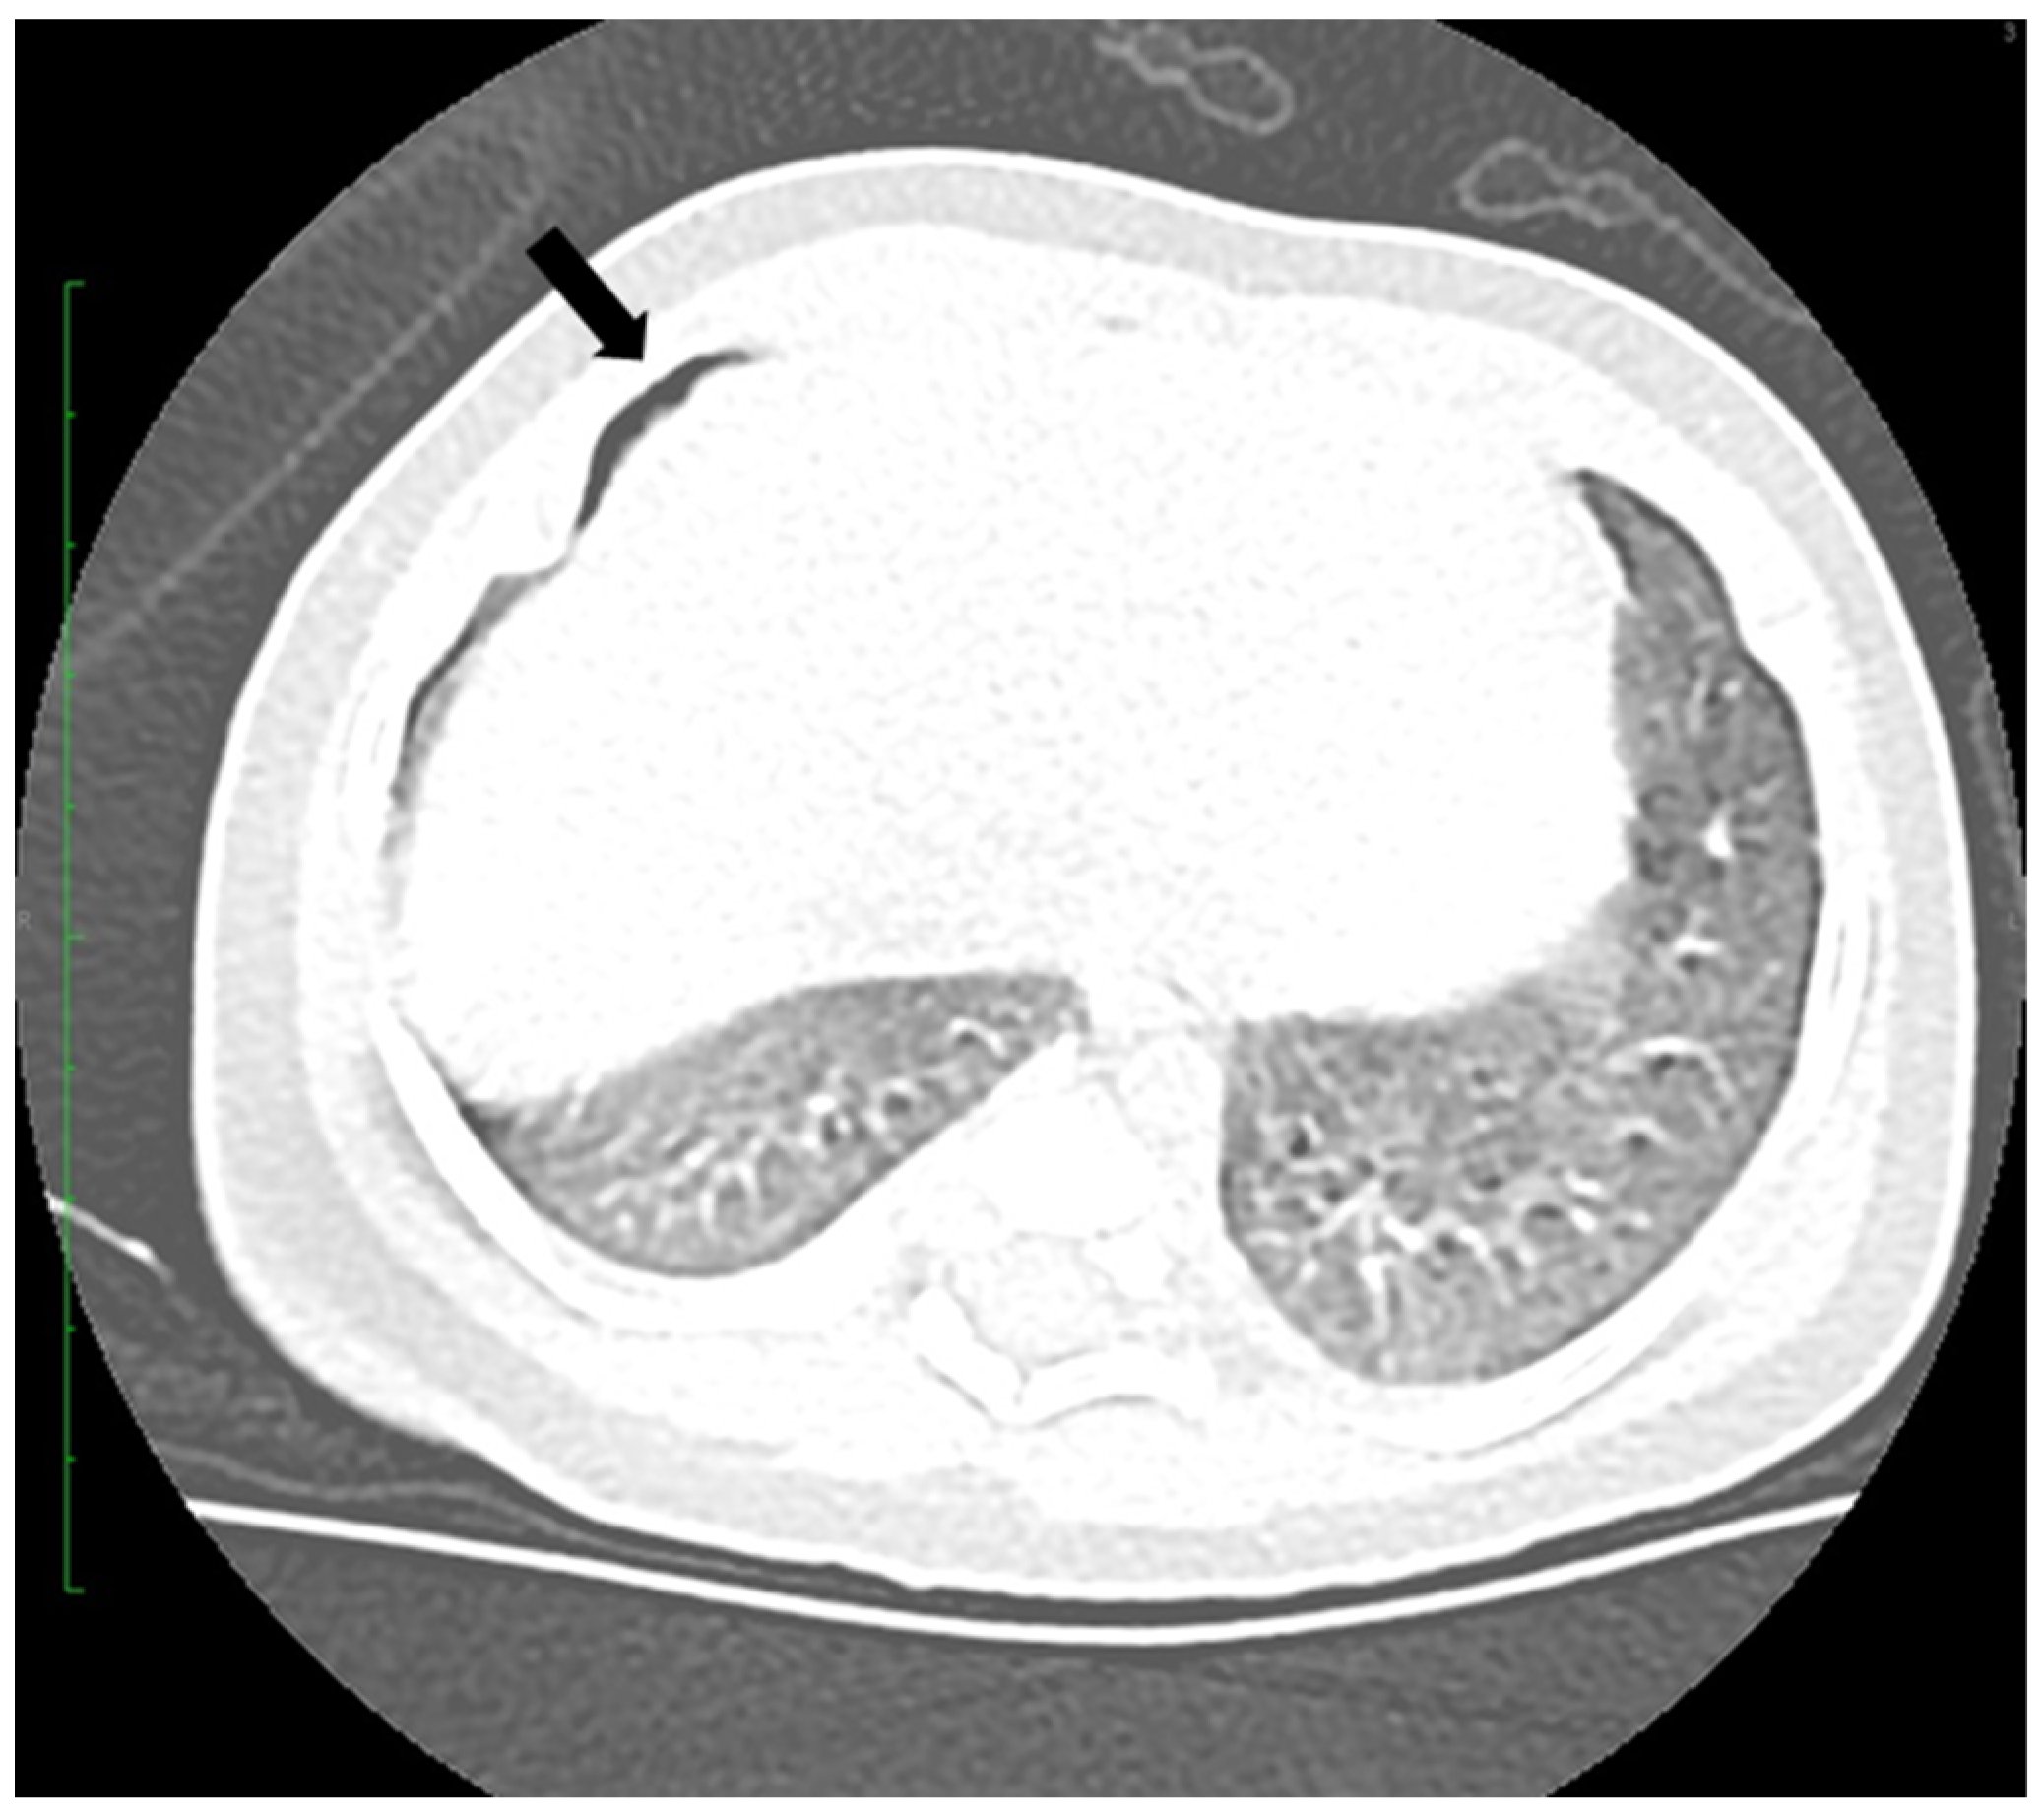

2.3. Case 3

2.4. Case 4